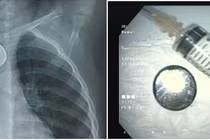

Qua thăm khám và chụp X-quang, các bác sĩ xác định dị vật nằm trong ổ bụng, ở ngang mức đốt sống. Bệnh nhi được chỉ định nội soi gắp dị vật khẩn cấp.

Dị vật trong dạ dày bé gái 6 tuổi. Ảnh BV

Thạc sĩ, bác sĩ Nguyễn Thị Mỹ Lệ - Phó Trưởng khoa Nhi tiêu hóa, Bệnh viện Sản - Nhi tỉnh chia sẻ, quá trình can thiệp nội soi gặp nhiều khó khăn do trong dạ dày bệnh nhi còn nhiều thức ăn.

Tuy nhiên, sau nhiều nỗ lực, ê-kíp đã gắp thành công kẹp tóc dài khoảng 7 cm ra khỏi dạ dày, đảm bảo an toàn cho bệnh nhi. Hiện tại bé đang được theo dõi sức khỏe sau nội soi.